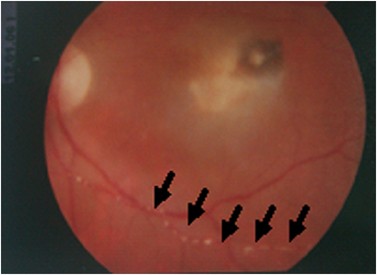

Toxoplasmosis Gondii Chorioretinitis

Toxoplasmic chorioretinitis - Wikipedia A typical chorioretinitis by toxoplasma Ocular Toxoplasmosis: Overview, Pathogenesis, Congenital Versus ... Toxoplasmosis - EyeWiki Fundus photograph of left eye showing active chorioretinitis of ... Toxoplasmosis Gondii Chorioretinitis